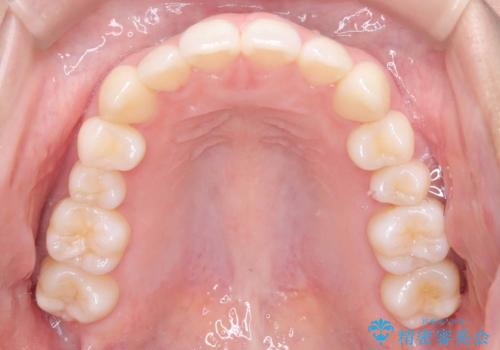

非抜歯矯正で八重歯を改善|短期間8か月で美しい歯並びに|インビザラインライト上顎のみで矯正

非抜歯で上顎のみインビザラインライトを使用して矯正を行いました。

短期間(約8か月)の治療で歯並びが整い、患者様も大変喜ばれました。